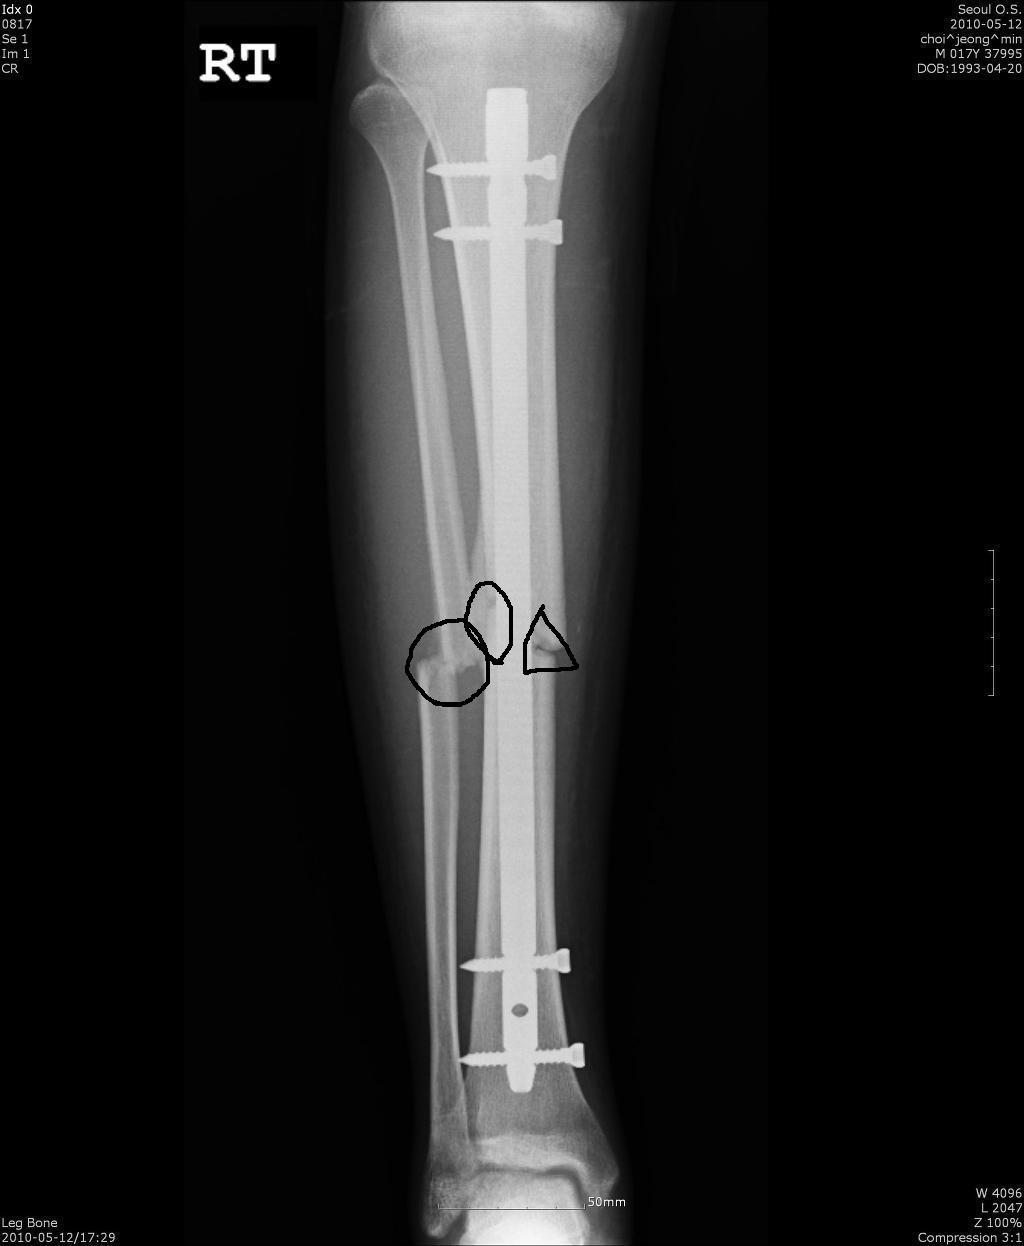

이사진은 5월달 그러니까 2월23이날 수술했으니까 거의 3개월 후사진입니다.

근데 지금 상태는 동그라미 친부분은 거의 다붙었는데 세모친부분이 저만큼이 아직도 안붙는다하더군요.

지금 6개월이 지났거든요.근데 제가 18살이긴한대 술.담배를 조금했었습니다 한동안 철없이요.

근데 요즘은 뼈가 안붙는데서 일절 끊었구요. 주치의 선생님 말씀으론 쇠를 좀더 일찍빼서 붙게 해보자고 하셨거든요.